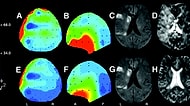

Beyni İncelenen Epilepsi Hastasından Beklenmedik Tepki: Tanrıyı Gördüm! Bazı tıbbi vakalar fazlasıyla eşsiz ve ilginç. Onları ilginç kılan, zihnimizin karmaşı... 17 Mayıs 2016